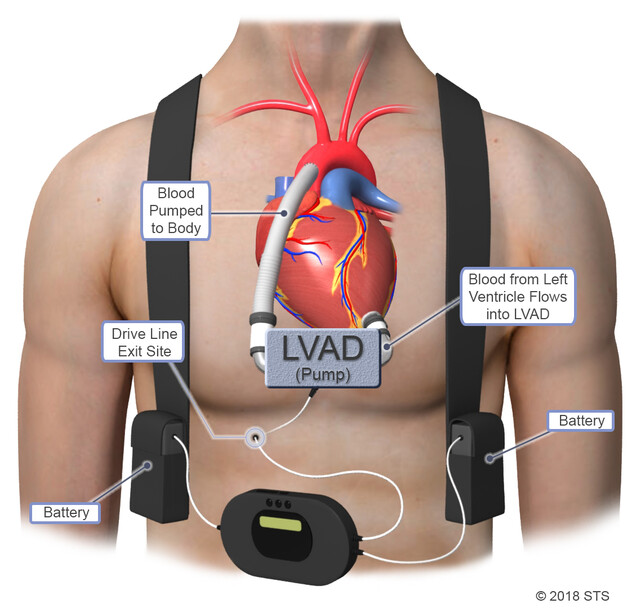

Introduction Heart failure affects millions of people worldwide, often making daily activities like walking, climbing stairs, or even resting difficult....